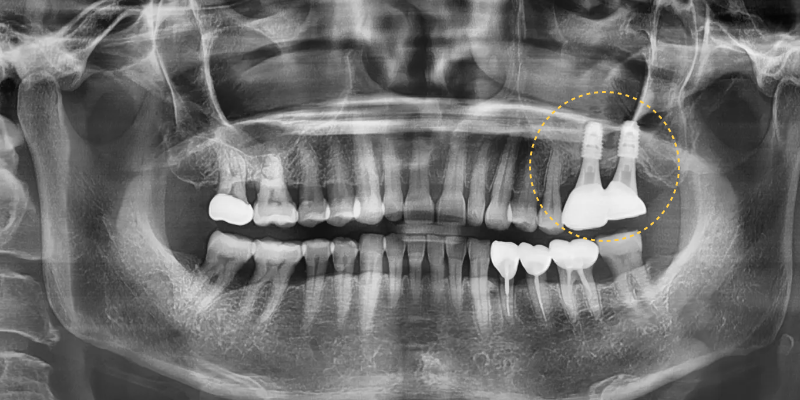

보철완료까지 전체 치료 기간은

약 10개월이 소요되었으며

파괴되었던 치조골이 점차 회복되면서

임플란트가 안정적으로 자리

잡는 과정을 확인할 수 있었습니다.

타원에서 임플란트가 어렵다는

소견을 들을 정도로 치조골의

파괴가 심했던 상태였지만,

단계적인 치조골이식술과 상악동거상술을 통해

충분한 뼈 재생을 이루어낼 수 있었고

그 결과 어금니 부위의 저작

기능도 함께 회복되었습니다.